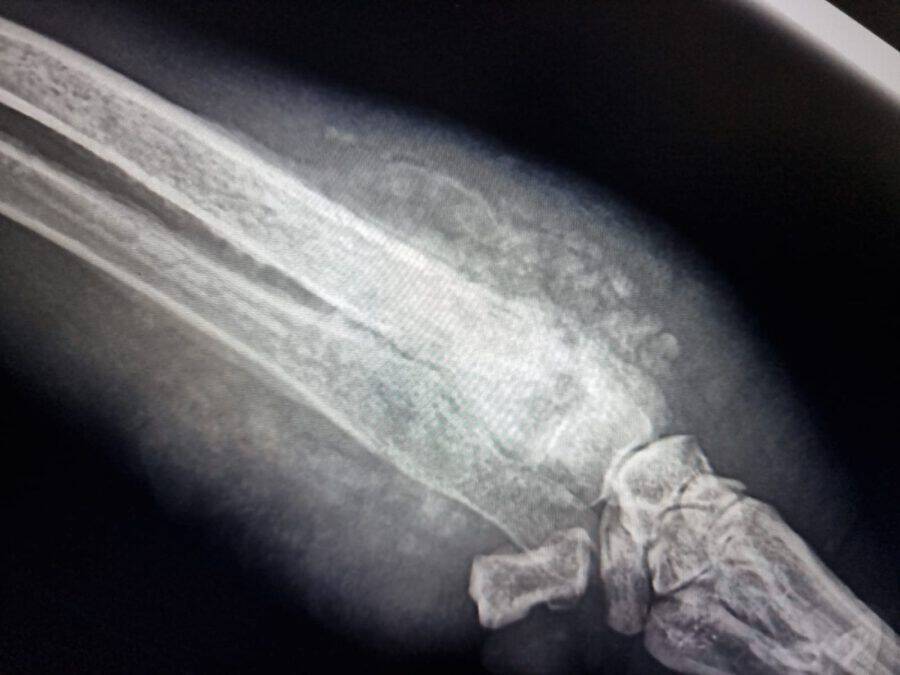

Anfang Dezember wurden wir auf diese arme Hündin aufmerksam gemacht, die zum Glück direkt von einer befreundeten Tierschützerin eingefangen und zu uns gebracht werden konnte. Für uns ging es gleich mit ihr zu unserem Spezialisten für Knochenkrankheiten und dort wurde sie gründlich untersucht. Es stellte sich heraus, dass Kalea leider eine weit fortgeschrittene Infektion innerhalb ihres Beinknochens hat. Sie bekommt nun Medikamente und wir hoffen alle sehr, dass diese anschlagen und wir ihr Bein retten können. Die Untersuchungen hat sie super artig über sich ergehen lassen und sie ist eine total liebe und zuckersüße Hündin, die es sich auch direkt bei unserer Elena auf dem Schoß bequem gemacht hat.

Leider konnten die Medikamente die Entzündung nicht hemmen und bei einem erneuten Tierarztbesuch wurde festgestellt, dass es wohl doch Knochenkrebs ist, der schon sehr stark fortgeschritten ist. Auch die Amputation des Beines hätte Kalea nicht retten können, sodass wir sie schweren Herzens gehen lassen mussten.